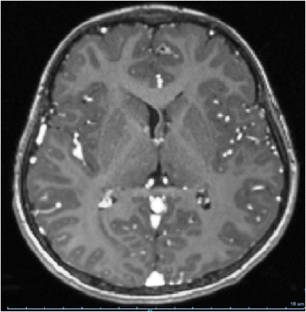

Subependymal giant cell astrocytomas (SEGAs) are low-grade intraventricular glial tumors that develop in 10–15% of patients with tuberous sclerosis complex; they often cause hydrocephalus and are potentially accessible to a surgical treatment. Our aim is to evaluate morbidity and results after surgery in symptomatic and asymptomatic patients.

Mean age at surgery was 10.7 years. The surgical decision was based on clinical signs of raised intracranial pressure due to hydrocephalus in 8 and on radiological findings without any clinical signs in the other 10 patients (increased in SEGA volume with or without ventricular enlargement). Surgical treatment consisted in a frontal trans-ventricular microsurgical approach in 17 patients and an endoscopic approach in 1. External ventricular drainage was placed in all the patients but 1. Ventriculoperitoneal shunting (VPS) became necessary in 6 patients, all of them presenting with a preoperative active hydrocephalus. Morbidity appeared very low with meningitis occurring in 1 patient. Resection was complete in 15 children with no recurrence during a mean follow-up of 5.25 years and incomplete in 3 requiring a second surgery.

Surgery of SEGA represents a very effective treatment with low morbidity and no mortality in the present series. In patients operated before the onset of clinical signs of hydrocephalus, internal VPS could be avoided whereas in others, an additional shunt surgery became necessary. This gives arguments in favor of a regular MRI surveillance in tuberous sclerosis complex patients with SEGA in order to best propose resective surgery once a growth of tumor and/or ventricular size have been confirmed but before raised intracranial pressure occurs.

Fig. 1